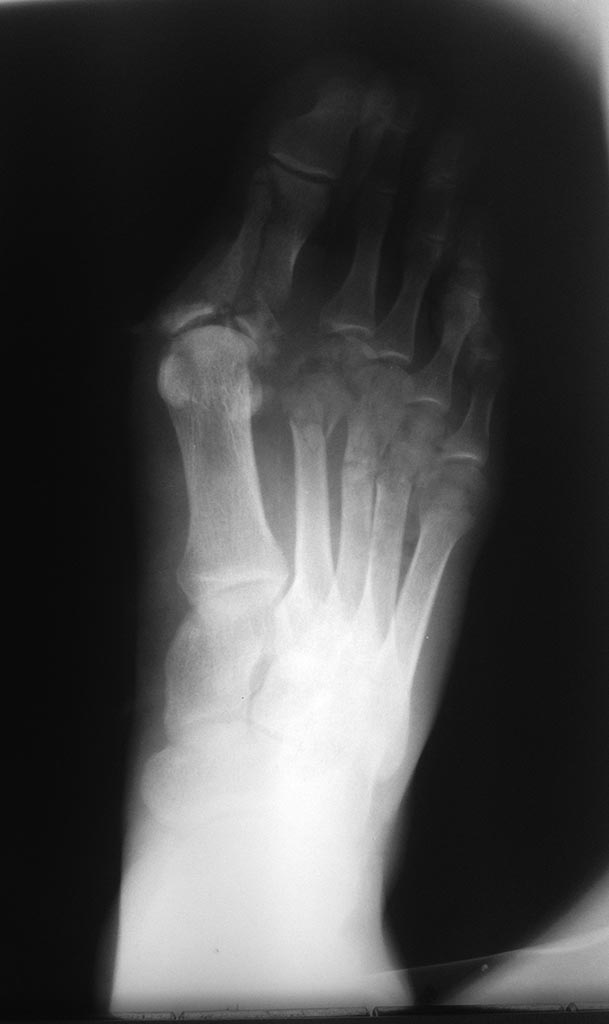

Здравствуйте ! Кто что сможет посоветовать ? Пациент 22 года упал

тяжёлый предмет на стопу (2 тонны) . На стопе выраженный отек, ушиблено-

рваная рана в области 1 плюсневой кости размером около 8см, сообщающаяся

с 1 плюсне фалагговым суставом. В голову лезут два варианта

лечения 1 . Наложение аппарата илизарова ( было бы неплохо, если бы кто-

нибудь отправил варианты компоновки ) 2 открытая репозиция основной

фаланги 1 пальца, а плюсневые консервативно.